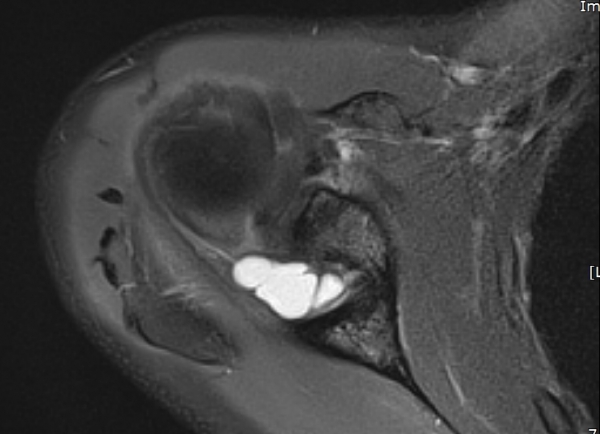

ÄÁº¤½ºÅ½ÃËÀÚ¸¦ ÀÌ¿ëÇÑ ¾î±ú µÚÂÊ È¾´Ü¸é°Ë»ç¿¡¼­ °üÀý¿Í ³»Ãø ¼ö¾× Àú·ù¿Í °üÀý¿Í¼ø ÆÄ¿­ÀÌ

°üÂûµÈ´Ù(»çÁø 3, 4, 5, 6).

large paralabral cyst